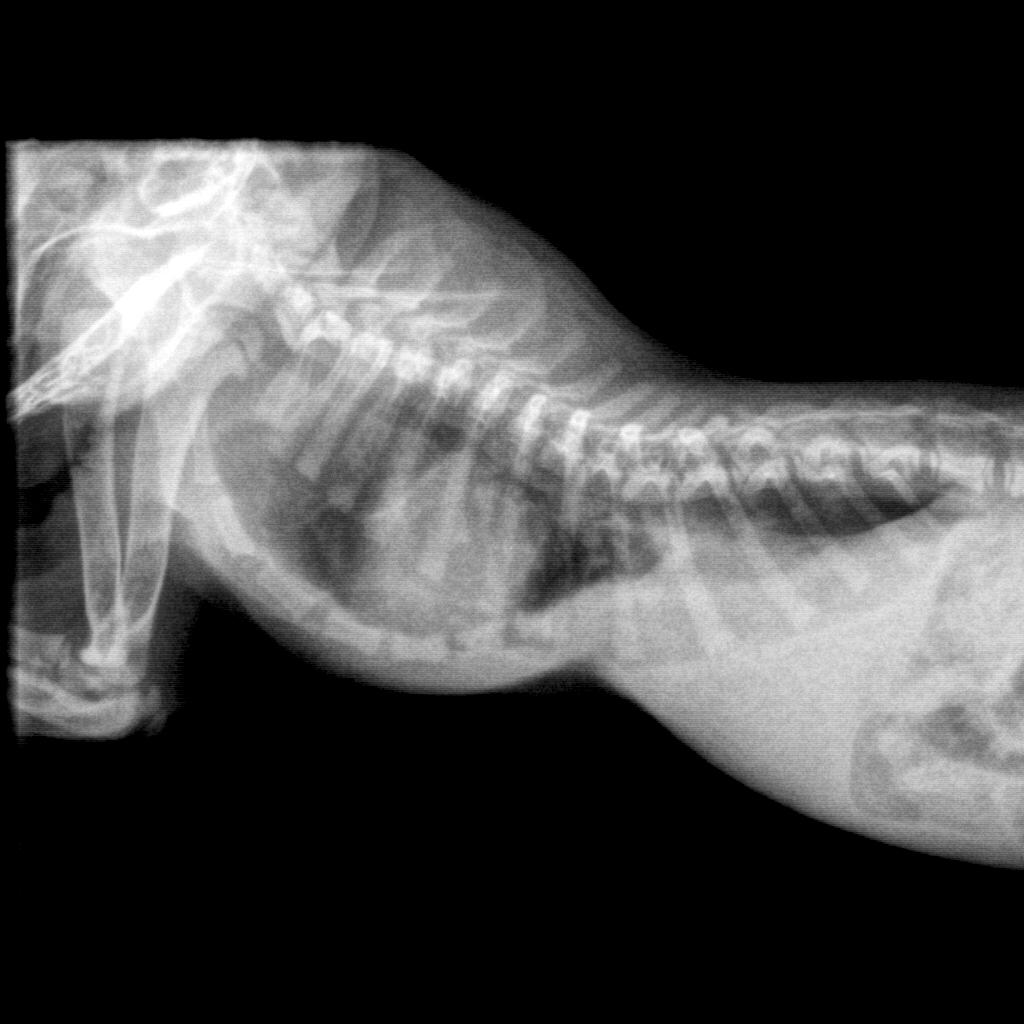

Perla è affetta da PECTUS EXCAVATUM, patologia che la farebbe morire entro poco perché crea problemi agli organi interni che non trovano spazio nel torace per potersi sviluppare.

Questa micina ha soltanto 54 giorni, e nei giorni scorsi Rosalba l’ha portata alla Clinica Roma Sud dove dovrà essere operata d’urgenza. Essendo l’operazione e il recupero fisico di Perla molto costoso, ed essendo le volontarie non sostenute pubblicamente da nessuno se non dai privati, Rosalba ha aperto una raccolta fondi per far fronte alle spese che sta e che dovrà sostenere.

Il delicato intervento al quale è stata sottoposta Perla è riuscito.

Ecco una foto-aggiornamento della piccolina.